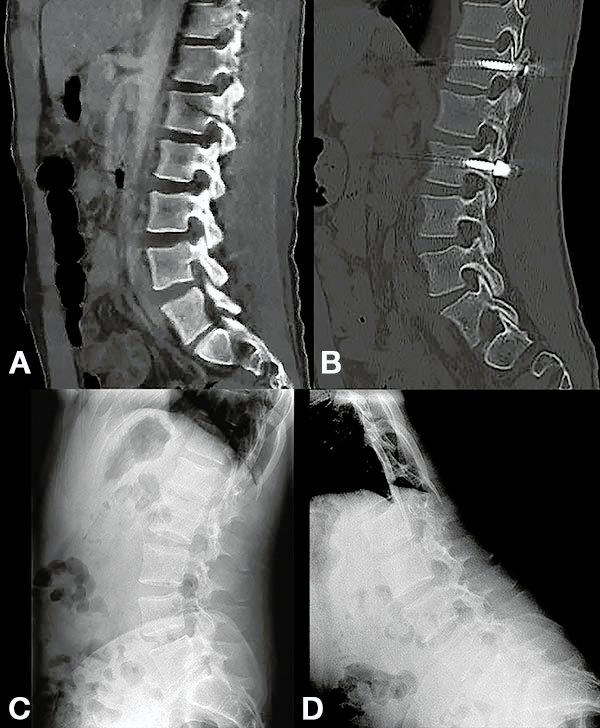

Figura 2:

Caso 24. A y B: Fractura horizontal que compromete cuerpo, pedículo izquierdo y apófisis espinosa de L1 (L1: B1; N1 AOSpine). C y D: Estabilización percutánea T12-L2.

Figura 3:

Caso 24. A: Fractura L1: B1; N1. B: Control 7 meses que evidencia consolidación. C y D: Retiro de osteosíntesis a los 9 meses con buena movilidad en las radiografías dinámicas de control.